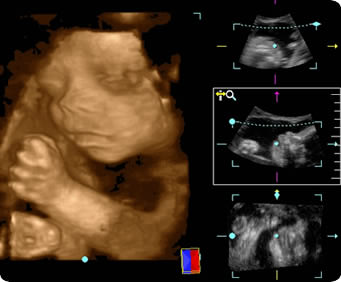

超音波検査画像